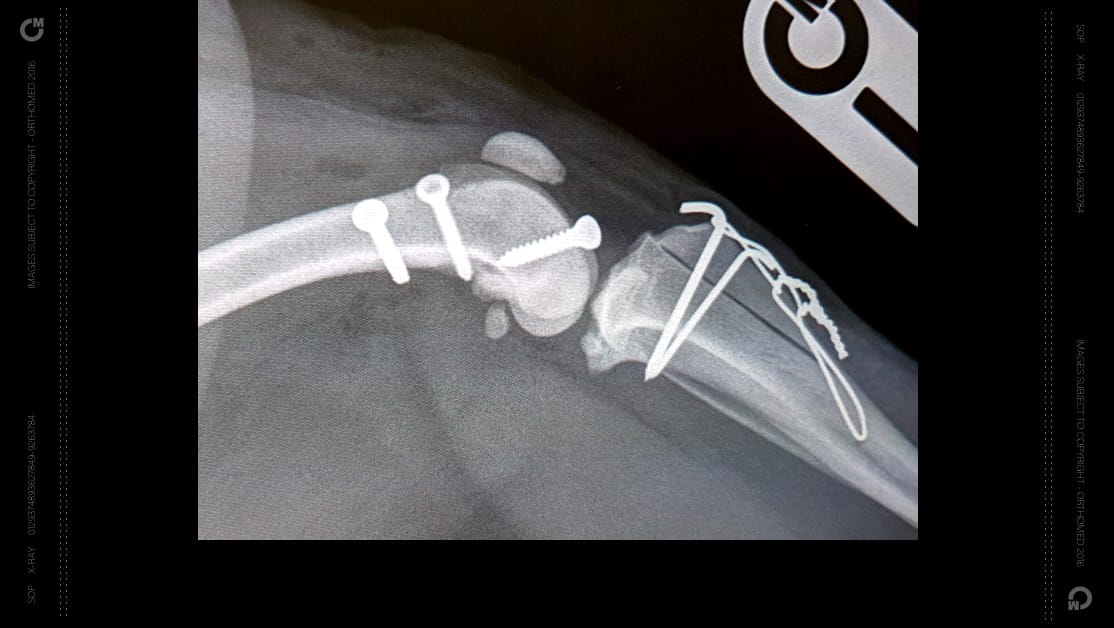

RidgeStop™ has been designed to provide surgeons with a cost effective alternative to sulcoplasty when carrying out procedures used to correct patella luxation. It uses a synthetic ridge held in place using standard cortical screws to build up the sides of the patella groove where it is insufficient or eroded due to degenerative conditions.

The ‘Ridge’, when correctly positioned acts as a barrier to prevent the patella slipping.

The aim of the surgery is to ensure the patella slides up and down within its groove without slipping to one side or the other, causing discomfort and lameness.

• Uses standard cortical bone screws

Each implant size has a corresponding drill guide, to ensure ideal placement of the implant. Depending on the implant size, they will require either two or three standard cortical bone screws, and the use of the drill guide allows not only ideal placement of the implant but also alignment of the divergent screw holes.